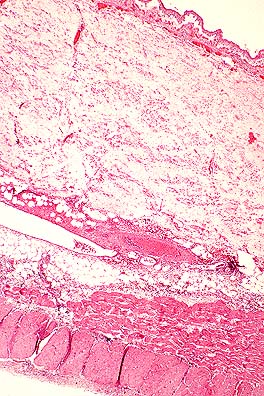

Marked hepatic portal fibrosis in a mouse injected with S. mansoni cercaria 3.5 months previously. (HE, 20X, 58K)

Contributor's Diagnosis and Comments: Liver: hepatitis, chronic, portal and bridging, multifocal, moderate, with granuloma formation, trematode eggs, pigment, and intravascular trematode parasites - etiology consistent with Schistosoma mansoni.

Schistosomes are digenetic trematodes that live within the blood vessels of their hosts. Their distribution is determined by the distribution of their intermediate hosts (a nonoperculated snail in the case of S. mansoni). Schistosome eggs hatch in the water releasing a ciliated miracidium which penetrates the snail. Cercariae develop in the snail and are released in the water where they are ingested or penetrate the skin to infect the host. Metacercaria migrate to the liver, pair within the portal circulation, reach maturity, and deposit eggs which penetrate capillary walls and leave the body via the feces or the urine to continue the life cycle.

Schistosomiasis is one of the most common causes of human morbidity and mortality. The adult parasites live in the host's veins and can incorporate host antigens, avoiding an immune response. The eggs that remain in tissues cause inflammation that progresses from neutrophils and eosinophils to granulomas with multinucleate giant cells. Urinary schistosomiasis has been associated with carcinomas of the urinary bladder in man and nonhuman primates.

AFIP Diagnosis: Liver: Hepatitis, portal and bridging, chronic, multifocal, moderate, with granulomas, trematode eggs, and intravascular trematodes, Swiss-Webster mouse, rodent, etiology consistent with Schistosoma mansoni.

Conference Note: Schistosomiasis is a snail-borne fluke infection prevalent in domestic animals, nonhuman primates, and humans in Asia, Africa, and other tropical and subtropical areas. Species that parasitize mammals include those of the genera Schistosoma, Hetrobilharzia and Orientobilharzia. The only schistosome of importance in the United States is Heterobilharzia americana, which has been reported in raccoons, bobcats and dogs in the southern United States. Schistosomes are different from other flukes in that they live in blood vessels, have separate sexes, have nonoperculated eggs with a spine, and do not have an encysted metacercaria stage.

Adult schistosomes, while alive in the veins, generally provoke little or no host response because they incorporate host antigens (primarily blood group antigens) into the outer membranous tegument and are therefore recognized as "self." Phlebitis with intimal proliferation and occasionally thrombosis may result from the presence of adult flukes. Vascular lesions are more severe when the adult worms die or are trapped at unusual sites. Eggs that escape into the tissues stimulate considerable inflammation. Penetration of the skin by cercariae results in urticaria, itching and formation of tiny nodules which elevate the epidermis. In humans, this often is caused by avian schistosomes and is commonly called "swimmer's itch."

The diagnosis of schistosomiasis can be readily made on histopathologic sections with the finding of intravascular trematodes and/or the characteristic spiny, non-operculated eggs.